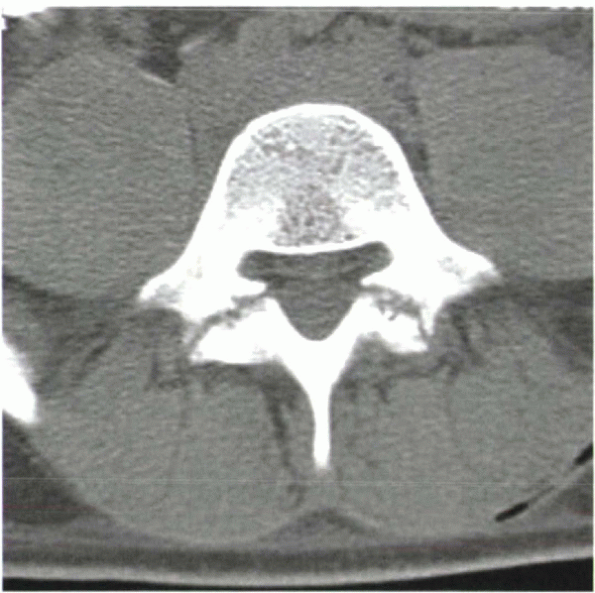

important disadvantage of MRI for the surgeon is the extreme

sensitivity of this technique to implanted metal, resulting in

artifacts that often render

the exam uninterpretable. Stainless steel instrumentation is ferromagnetic and leads to significant artifact (Fig. 2-3),

![]() |

|

Figure 2-3 Postsurgical MRI shows significant hardware artifact from ferromagnetic metallic implants.